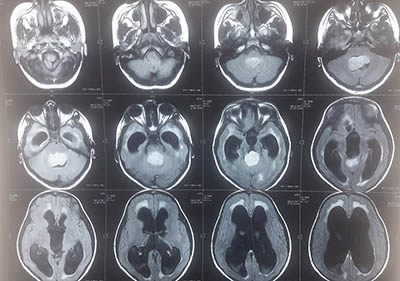

His surgical and clinical expertise cover the entire spectrum of brain and spine diseases. He specially trained in Endoscopic and Microscopic Neurosurgery. A bright student throughout his education he has to his name various tedious neurosurgical procedures.